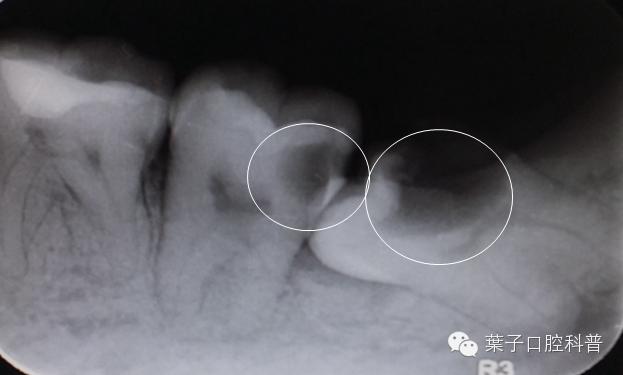

智齿以及前面的第二磨牙龋坏

拔智齿十大危害,拔智齿利与弊